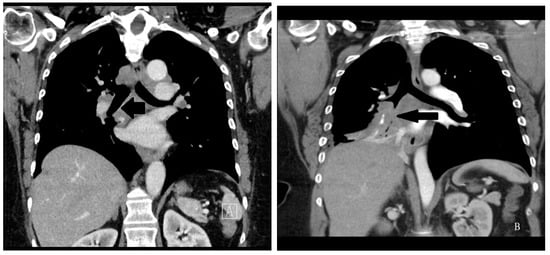

Figure 7.

(A) Left figure: Chest CT sagittal image of mediastinal lymph nodes from sarcoidosis. The lymph nodes do not appreciably disturb airway patency, and the right bronchus intermedius is completely unobstructed (arrow); (B) Right figure: Chest CT sagittal image of mediastinal lymph nodes from small cell lung carcinoma. The lymph nodes do not respect anatomic boundaries and compromise the right bronchus intermedius (arrow).